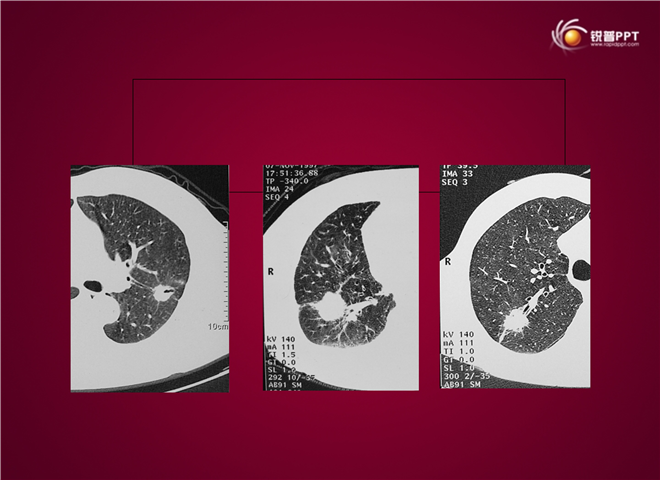

23_CT读片基础